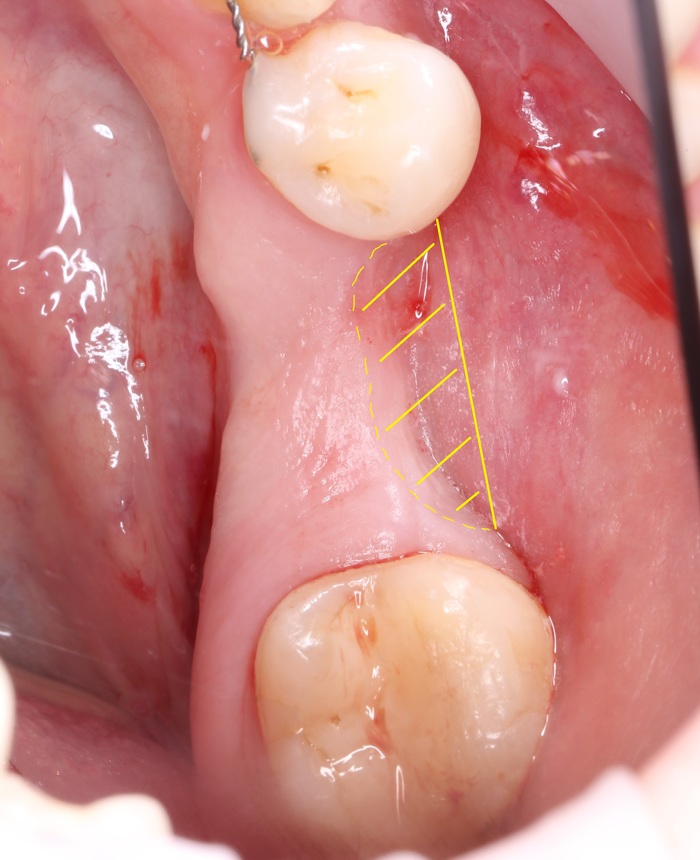

После того, как анестезия подействовала, при помощи скальпеля производится разрез, а с помощью распатора – скелетирование кости. (отделение надкостницы от компактного вещества кости)

Разрез: